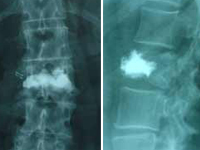

Cifoplastia_05Mujer, 55 años. Fractura aplastamiento derecho de L2 . Cifoplastia_03

Cifoplastia con balón. Fractura aplastamiento DX y DXI

Cifoplastia de L2